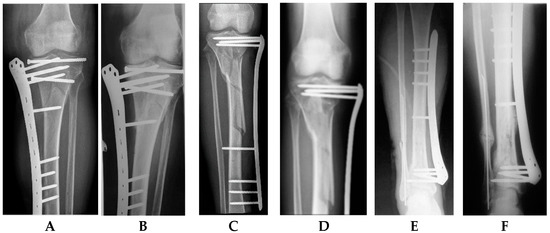

Single-Stage Externalized Locked Plating for Treatment of Unstable Meta-Diaphyseal Tibial Fractures

by Biser Makelov, Dominic Mischler, Peter Varga, Theerachai Apivatthakakul, James W. A. Fletcher, Deyan Veselinov, Till Berk, Dimitur Raykov and Boyko Gueorguiev

J. Clin. Med. 2023, 12(4), 1600; https://doi.org/10.3390/jcm12041600 - 17 Feb 2023

Cited by 3 | Viewed by 4965

(1) Background: Unstable meta-diaphyseal tibial fractures represent a heterogeneous group of injuries. Recently, good clinical results have been reported when applying a technique of externalized locked plating in appropriate cases, highlighting its advantage in terms of less additional tissue injury compared with conventional [...] Read more.

(1) Background: Unstable meta-diaphyseal tibial fractures represent a heterogeneous group of injuries. Recently, good clinical results have been reported when applying a technique of externalized locked plating in appropriate cases, highlighting its advantage in terms of less additional tissue injury compared with conventional methods of fracture fixation. The aims of this prospective clinical cohort study were, firstly, to investigate the biomechanical and clinical feasibility and, secondly, to evaluate the clinical and functional outcomes of single-stage externalized locked plating for treatment of unstable, proximal (intra- and extra-articular) and distal (extra-articular), meta-diaphyseal tibial fractures. (2) Methods: Patients, who matched the inclusion criteria of sustaining a high-energy unstable meta-diaphyseal tibial fracture, were identified prospectively for single-stage externalized locked plating at a single trauma hospital in the period from April 2013 to December 2022. (3) Results: Eighteen patients were included in the study. Average follow-up was 21.4 ± 12.3 months, with 94% of the fractures healing without complications. The healing time was 21.1 ± 4.6 weeks, being significantly shorter for patients with proximal extra- versus intra-articular meta-diaphyseal tibial fractures, p = 0.04. Good and excellent functional outcomes in terms of HSS and AOFAS scores, and knee and ankle joints range of motion were observed among all patients, with no registered implant breakage, deep infection, and non-union. (4) Conclusions: Single-stage externalized locked plating of unstable meta-diaphyseal tibial fractures provides adequate stability of fixation with promising clinical results and represents an attractive alternative to the conventional methods of external fixation when inclusion criteria and rehabilitation protocol are strictly followed. Further experimental studies and randomized multicentric clinical trials with larger series of patients are necessary to pave the way of its use in clinical practice. Full article

(This article belongs to the Section Orthopedics)

Show Figures

Figure 1